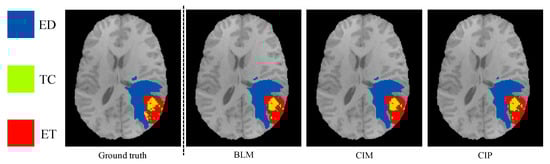

3.1. Segmentation Accuracy for Multimodal MR Model Training